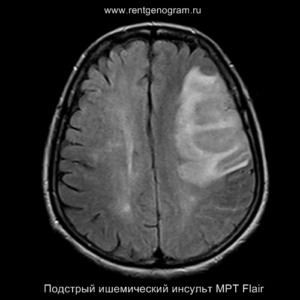

Подострая фаза (24 часа — 6 недель)

На подостром этапе происходит разрушение гематоэнцефалического барьера, что приводит к вазогенному отеку, увеличивая объем ишемического инфаркта, возникновение масс-эффекта и возможного вклинения в случае обширного поражения (например, вклинение поясной извилины под фалькс или миндалин мозжечка в большое затылочное отверстие).

Разрушение гематоэнцефалического барьера (ГЭБ) приводит к накоплению контрастного вещества в области ишемического инсульта, используя технику контрастирования по «гиральному типу».

Когда в мозговых артериях происходит реканализация кровотока, это может привести к образованию геморрагических пропитываний и кровоизлияний («красный компонент» ишемического инфаркта), что будет отображаться на МРТ как ↑ на Т1 и Т2*, а на КТ — как участки с гетерогенной повышенной плотностью. На более поздних этапах подострой стадии наблюдается нормализация ранее повышенных показателей DWI и ADC, известная как «псевдонормализация» диффузии.